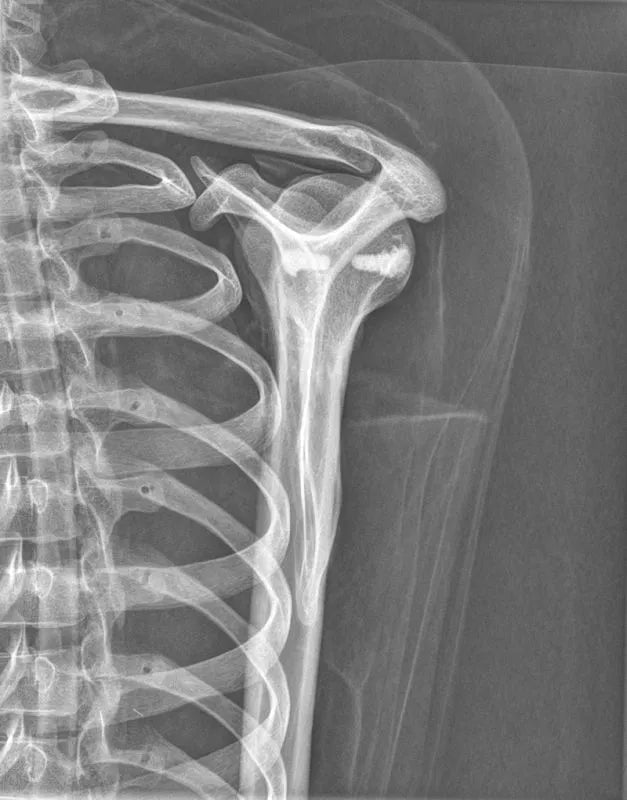

The whole-body X-ray phantom serves for practical training in projection radiography as well as in positioning and positioning techniques. It enables the production of realistic X-ray images under training conditions and depicts anatomical structures in their natural size.

The phantom contains a natural human skeleton. Additionally, the outlines of the larynx, lungs, heart, and kidneys are integrated, appearing as shadows on the X-ray images. This allows for the creation of images that accurately reflect the conditions found in patients. The use of a real skeleton enables the identification of bony landmarks that are not visible in plastic models.

The joints are mounted with full mobility, allowing positioning in common radiological standard positions, including special positions such as the frog position and pronation and supination of the forearm. The arms can be raised, so the phantom can also be used for bone examinations in CT scans. Particular attention was paid during assembly to the realistic representation of the joint spaces.

Each phantom is a handcrafted, unique piece. Variations in size, design, and appearance are possible. Depending on the model, pathological findings may be present. The revised design was developed in collaboration with a German training institution for medical-technical radiology assistants and meets the requirements of modern training concepts.